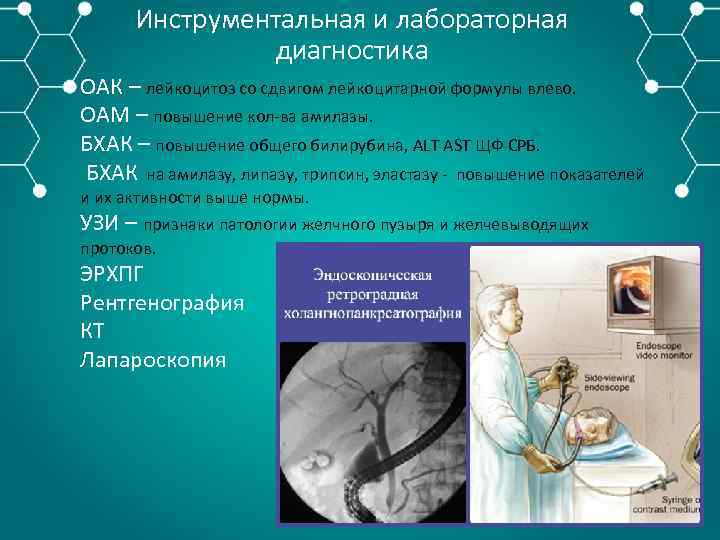

Инструментальная и лабораторная диагностика ОАК – лейкоцитоз со сдвигом лейкоцитарной формулы влево. ОАМ – повышение кол ва амилазы. БХАК – повышение общего билирубина, ALT AST ЩФ СРБ. БХАК на амилазу, липазу, трипсин, эластазу повышение показателей и их активности выше нормы. УЗИ – признаки патологии желчного пузыря и желчевыводящих протоков. ЭРХПГ Рентгенография КТ Лапароскопия